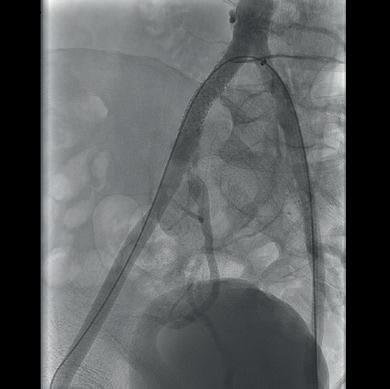

“Critical” importance of lifelong surveillance after EVAR headlines newly published 10-year ENGAGE data

Ten-year data highlight the long-term efficacy and durability of the Endurant stent graft (Medtronic) in abdominal aortic aneurysm (AAA) patients who survived beyond five years post-enrolment in the ENGAGE registry. However, researchers also draw attention to the incidence of late events in this extended follow-up cohort, which they say underscores the need for lifelong surveillance. These findings were recently published online in the European Journal of Vascular and Endovascular Surgery (EJVES).

ENGAGE IS A MEDTRONIC-SPONSORED, observational, multicentre, non-randomised, prospective global registry designed to shed light on the long-term outcomes of endovascular aneurysm repair (EVAR). In their EJVES paper, Hence Verhagen (Erasmus University Medical Centre Rotterdam, Rotterdam, the Netherlands) and a team of coinvestigators from across Europe, the USA and Canada note that the registry will be the first to report long-term outcomes of real-world, global AAA patients with the Endurant stent graft.

Verhagen and colleagues share that inclusion criteria for the registry were “minimal” and allowed for the incorporation of patients who fell outside the instructions for use guidance. Exclusion criteria, meanwhile, were “high probability of non-adherence to follow-up requirements, or concurrent participation in another trial that could confound results”. The authors note that clinical and imaging data were continuously collected to evaluate treatment efficacy through 10 years.

cohort. The remaining 873 patients made up a nonextended follow-up cohort.

In EJVES, the authors report the continued longterm efficacy and durability of the Endurant stent graft. They share that freedom from site-reported all-cause mortality and clinical event committee (CEC)-adjudicated aneurysm-related mortality for the extended follow-up cohort was 75.7% and 97.3% through 10 years, respectively.

Furthermore, through 10 years, Verhagen et al note that each rate for freedom from aneurysm-related rupture (96.2%) and aneurysm-related interventions (71.4%) was comparable with the respective rate through the first five years.

Among several other datapoints, the authors detail that late re-interventions (n=72) were associated with type Ia endoleaks (18/72), type II endoleaks (18/72), and type Ib endoleaks, adding that, at 10 years, 64.1% of patients exhibited sac regression, 19.2% were sac stable, and 16.8% had sac expansion.

when the protocol was amended and thus the data in the extended follow-up cohort (more than five to 10 years) do not represent the full ENGAGE cohort,” they write, for example. However, the authors state that event rates in the extended and non-extended follow-up cohorts were similar from zero to five years and that the team provided baseline differences in the extended follow-up cohort “to allow readers to put outcomes in context and be transparent with any potential bias of the patient population”.

The lack of a control group was another potential drawback, Verhagen and team note. Consequently, the results “could only be indirectly compared with results from other clinical studies”. Among other limitations, the authors highlight the fact that follow-

up compliance over the more than five to 10-year period decreased due in part to challenges with data collection during the COVID-19 pandemic.

Of the 1,263 patients enrolled in the ENGAGE registry, Verhagen and colleagues state that 390 reconsented for follow-up from more than five through 10 years, constituting an extended follow-up

Verhagen and colleagues do highlight some limitations of their paper. “Potential bias was introduced as a subset of patients and sites did not reconsent from the original ENGAGE population

In the conclusion of their paper, the authors also draw attention to the fact that “this study was the first to demonstrate long-term performance and durability of the Endurant stent graft for aortic aneurysm treatment.” They also home in on the incidence of late events. “Different factors led to reintervention in the later years,” they state, noting that this supports current recommendations of lifelong surveillance.

“The authors suggest that lifelong surveillance is critical for EVAR patients due to the incidence of late events,” Verhagen and colleagues write.